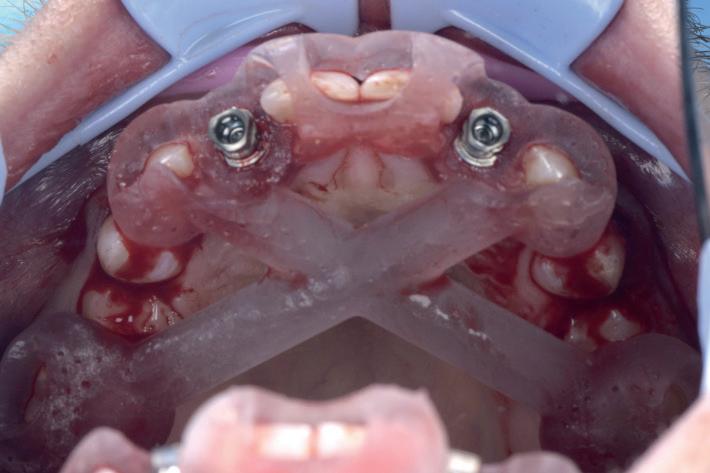

CASE STUDY

Guided implant approach for reproducible results, page 28